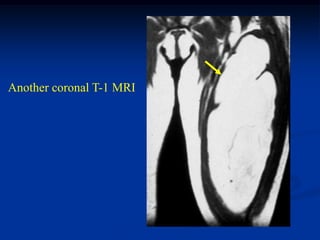

Case #276

64 year male with spindle cell lipoma proximal forearm

Sagittal T-1 MRI

Axial T-1 MRI

Axial proton density MRI